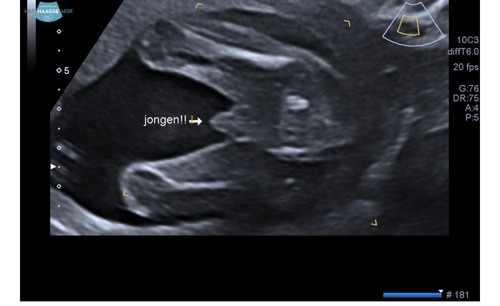

De vergelijking houdt op bij billen en benen. Het grote verschil is dat op jouw foto geen schaamlippen te zien zijn. En op de foto van TS wel. Behoorlijk duidelijk zelfs.

3 jaar geleden

De vergelijking houdt op bij billen en benen. Het grote verschil is dat op ...

Geel = billen en benen Roze = schaamlippen